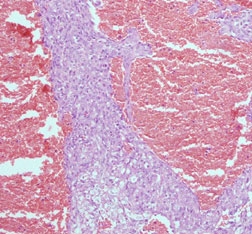

Mass on right auricle (x100)